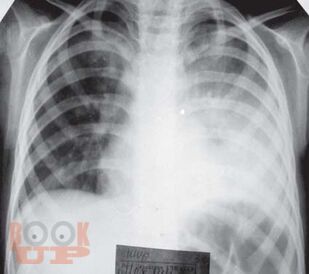

В данном томе многотомного руководства по детским болезням рассмотрены актуальные вопросы пульмонологии, систематизированные в виде современных представлений о заболевании органов дыхания. Приведены новейшие теоретические и клинические данные по анатомо-функциональной характеристике, этиологии, патогенезу, эпидемиологии, патоморфологии, патофизиологии, классификации заболеваний. Представлены методы диагностики и дифференциальной диагностики в детской пульмонологии. Даны практические рекомендации по лечению отдельных форм пульмонологических заболеваний и проведения реабилитационных мероприятий. Руководство иллюстрировано фотокопиями рентгенограмм, томограмм и др.